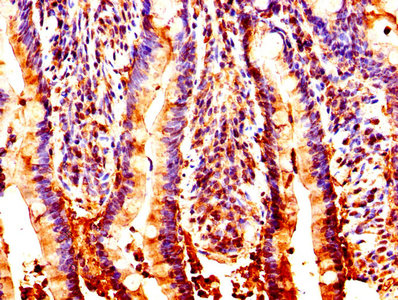

IHC image of CSB-PA016146HA01HU diluted at 1:200 and staining in paraffin-embedded human lung cancer performed on a Leica BondTM system. After dewaxing and hydration, antigen retrieval was mediated by high pressure in a citrate buffer (pH 6.0). Section was blocked with 10% normal goat serum 30min at RT. Then primary antibody (1% BSA) was incubated at 4°C overnight. The primary is detected by a biotinylated secondary antibody and visualized using an HRP conjugated SP system.